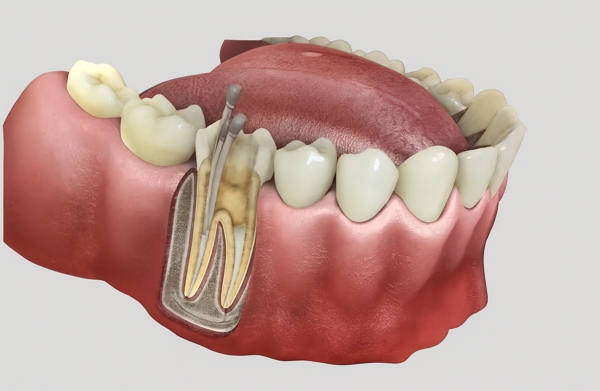

Es un tratamiento dental que consiste en limpiar y sellar el interior de un diente dañado o infectado (la pulpa), eliminando el tejido enfermo para salvar la pieza dental y evitar su extracción.

- Acceso: El dentista crea una pequeña abertura en la corona del diente para acceder a la pulpa.

- Limpieza: Se extrae la pulpa infectada o dañada, se limpian y desinfectan los conductos radiculares.

- Obturación: Los conductos vacíos se rellenan con un material biocompatible y se sella la apertura.